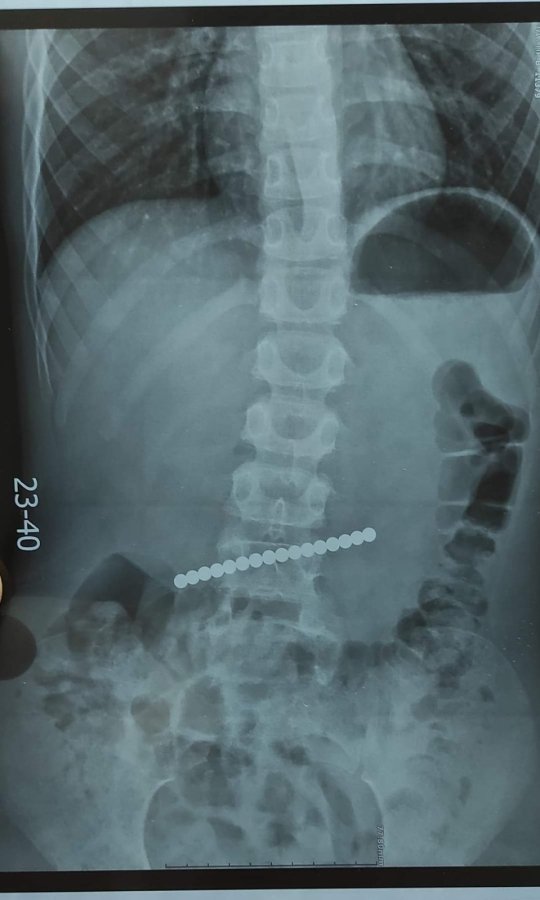

17 липня до Вінницької обласної дитячої клінічної лікарні надійшли чотири звернення через сторонні тіла у шлунково-кишковому тракті дітей віком від 3 до 10 років.

«Лікар-ендоскопіст дитячої обласної лікарні Артур Москаль зазначив, що всі випадки сталися після 23:00, коли діти проковтнули сторонні предмети. Особливу небезпеку становлять магніти, батарейки, монети та дрібні прикраси», - йдеться у повідомленні.